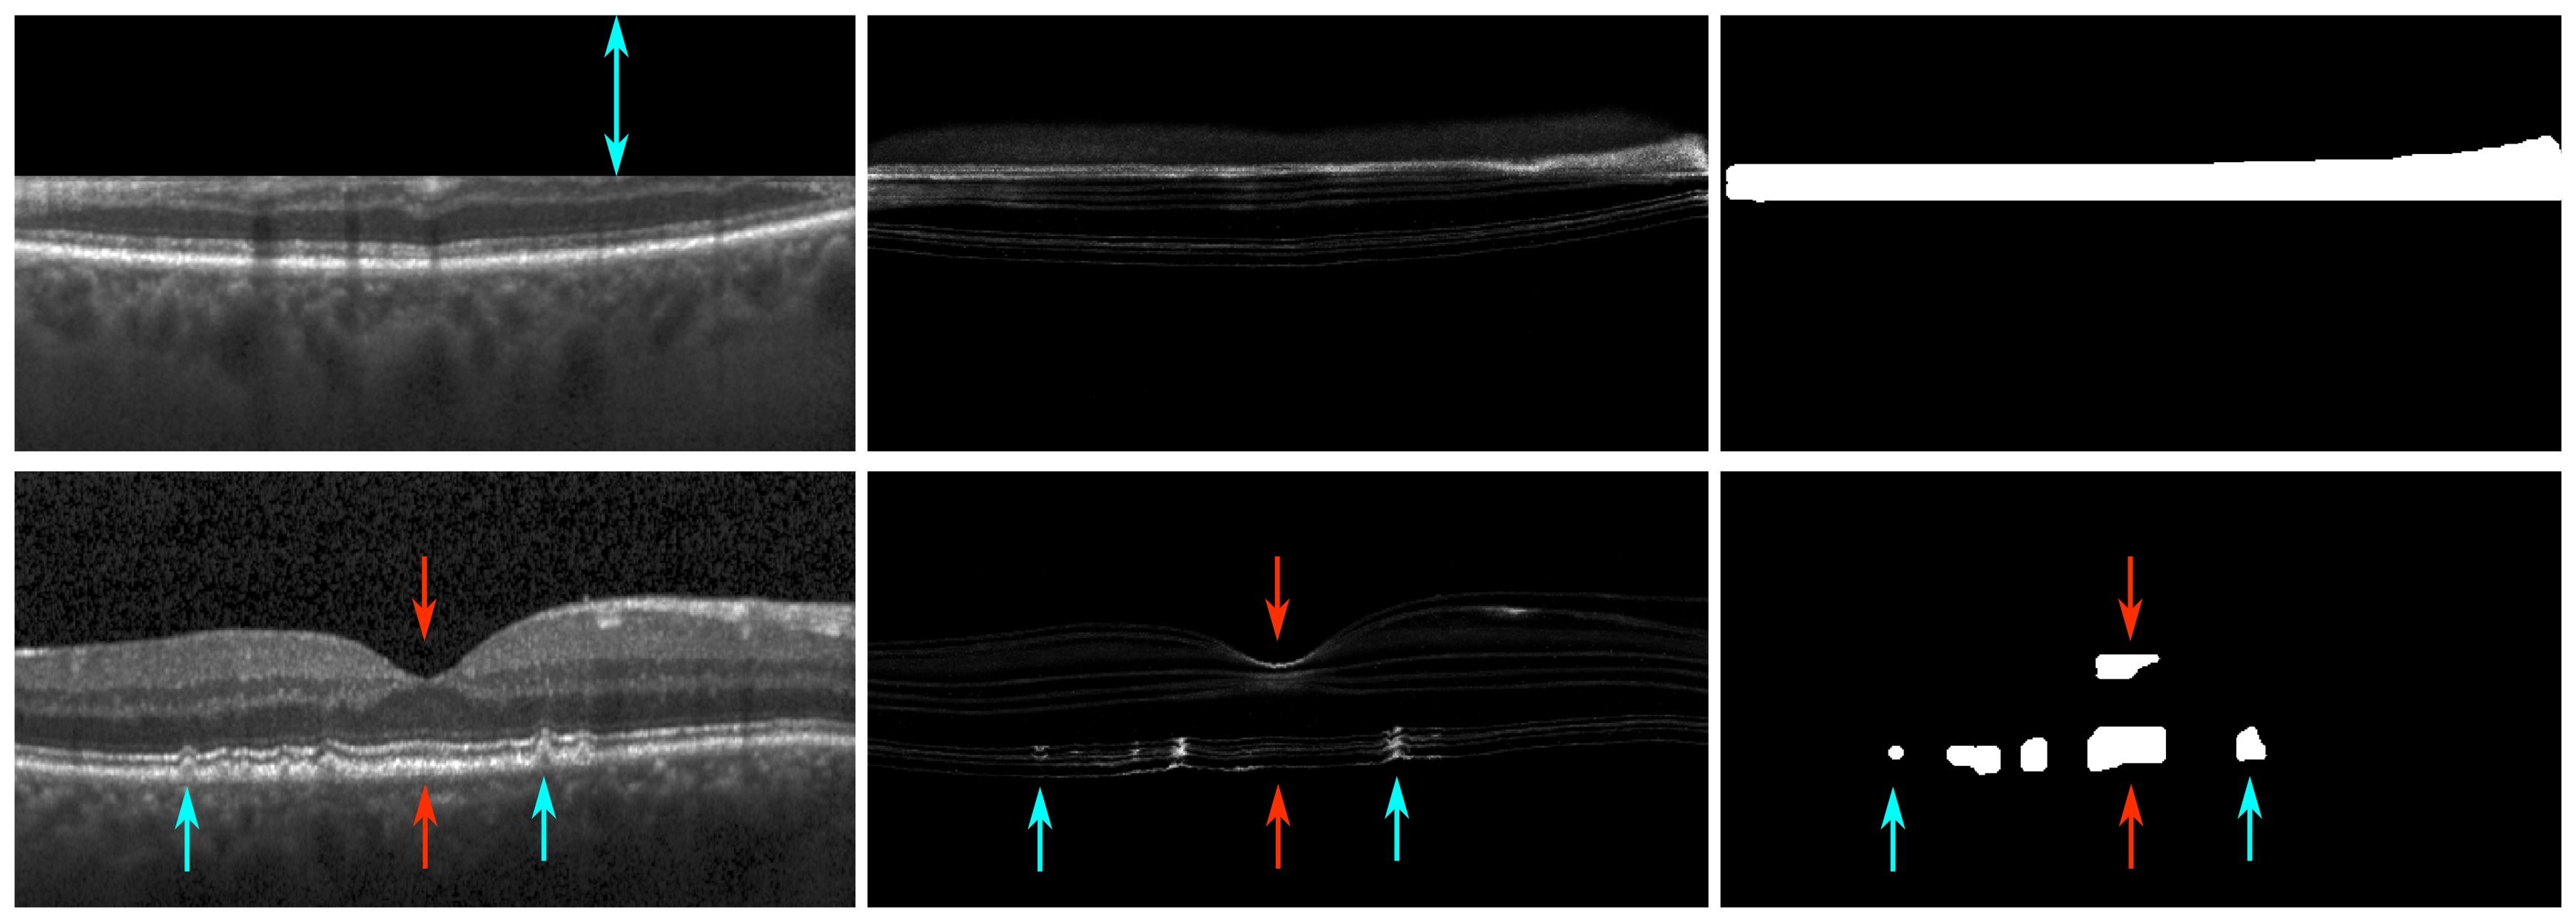

Figure 11: Qualitative results of the proposed method on (a) DME, (b) RVO and (c) GA cases.

Refer to caption

Figure 12: Anomaly detection in normal scans. Two B-scans from the normal evaluation dataset with the largest anomalous area are shown. From left to right: Original B-scans, uncertainty maps and corresponding anomaly segmentation results. Top row: cut edge artifact (blue arrow). Bottom row: small drusen (blue arrows) and false positives (red arrows).

Fig. 10 presents scatter plots showing the average number of anomalous pixels per B-scan for each diseased/healthy volume in our volume-wise classification experiments. As in Fig. 9, it can be seen that this feature is an almost perfect predictor for this application. Qualitative results of the central B-scan of DME, RVO and GA cases, respectively, are presented in Fig. 11. The anomalous region detected in Fig. 11 (a) covers parts of the retina with intraretinal cystoid fluid. The segmentation in Fig. 11 (b) shows a similar behaviour, although it also includes areas of intraretinal hyperreflective foci. Finally, Fig 11 (c) illustrates that our method is also capable of selectively detecting areas of RPE atrophy and neurosensory thinning in eyes with GA.

Finally, it is worth pointing out a potential limitation of the majority-ray-casting algorithm, related to the internal distribution and localization of anomalies within the retina. Since the post-processing algorithm assumes that areas surrounded by uncertainties are anomalous (Fig. 2), there could be specific clinical scenarios in which this assumption does not hold: e.g. in between three independent anomaly detections (Fig. 12, bottom row, bottom red arrow). Hence, this can lead to oversegmentation. In some cases, we also observed false positives in the fovea depression, caused by a thinning in the top retinal layers (Fig. 12, bottom row, top red arrow). Nevertheless, anomaly detection approaches are needed to reach high levels of sensitivity when applied for screening or detecting pathological areas, and false positives are tolerated to a certain extent. Therefore, oversegmentation might not harm the final application. Moreover, the volume-wise disease detection experiment showed perfect separation between diseased and healthy subjects using only the amount of abnormal area for discrimination.